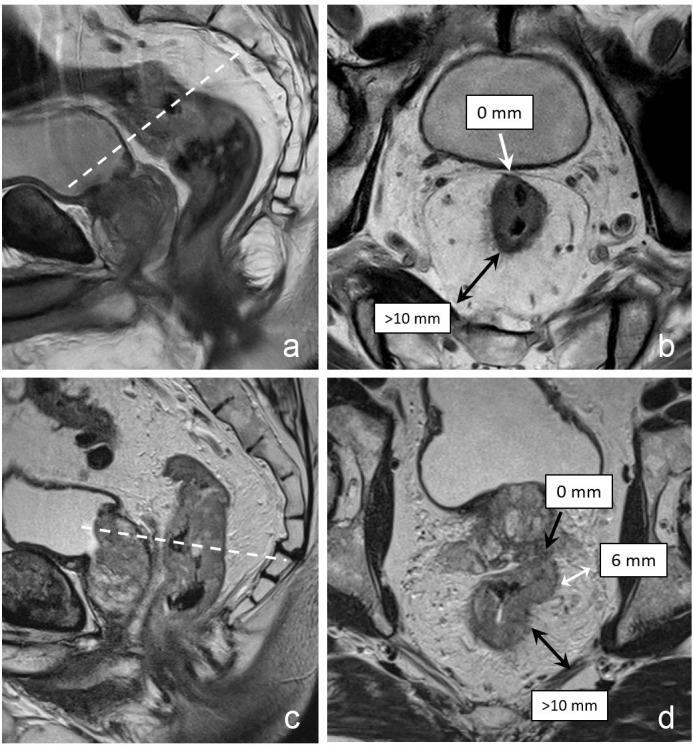

Twenty-one radiologists (12 countries) staged 75 rectal cancers on MRI using a structured reporting template. Interobserver agreement (IOA) was calculated as the percentage agreement between readers (categorical variables) and Krippendorff's α (continuous variables). Agreement with an expert consensus served as a surrogate standard of reference to estimate diagnostic accuracy. Polychoric correlation coefficients were used to assess correlations between diagnostic confidence and accuracy (=agreement with expert consensus).

Uniformity to diagnose high-risk (≥cT3 ab) versus low-risk (≤cT3 cd) cT-stage, cN0 versus cN+, lateral nodes and tumour deposits, MRF and sphincter involvement, and solid versus mucinous tumours was high with IOA > 80% in the majority of cases (and >80% agreement with expert consensus). Results for assessing extramural vascular invasion, cT-stage (cT1-2/cT3/cT4a/cT4b), cN-stage (cN0/N1/N2), relation to the peritoneal reflection, extent of sphincter involvement (internal/intersphincteric/external) and morphology (solid/annular/semi-annular) were considerably poorer. IOA was high (α = 0.72-0.84) for tumour height/length and extramural invasion depth, but low for tumour-MRF distance and number of (suspicious) nodes (α = 0.05-0.55). There was a significant positive correlation between diagnostic confidence and accuracy (=agreement with expert consensus) (p < 0.001-p = 0.003).

对于诊断高危(≥cT3ab)与低危(≤cT3cd)cT 分期、cN0 与 cN+、侧方淋巴结和肿瘤沉积、MRF 和括约肌侵犯、实体瘤与黏液瘤,大多数情况下 IOA >80%,一致性>80%(与专家共识一致),具有高度一致性。对于评估外膜血管侵犯、cT 分期(cT1-2/cT3/cT4a/cT4b)、cN 分期(cN0/N1/N2)、与腹膜反射的关系、括约肌侵犯程度(内部/内括约肌/外部)和形态(实体/环状/半环状)的一致性则较差。肿瘤高度/长度和外膜侵犯深度的 IOA 较高(α=0.72-0.84),而肿瘤-MRF 距离和可疑淋巴结数量的 IOA 较低(α=0.05-0.55)。诊断信心与准确性(与专家共识一致)之间存在显著正相关(p<0.001-p=0.003)。